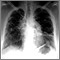

Cor pulmonale

Es la insuficiencia del lado derecho del corazón provocada por una hipertensión arterial prolongada en las arterias pulmonares y en el ventrículo derecho del corazón.

La presión alta en las arterias de los pulmones se denomina hipertensión pulmonar. El lado derecho del corazón tiene una mayor dificultad para bombear sangre cuando esto sucede. Si esta presión alta se presenta por un tiempo más prolongado, esto ejerce tensión sobre el lado derecho del corazón, llevando a que se presente cor pulmonale.

Pruebas y exámenes

Los siguientes exámenes pueden ayudar a diagnosticar el cor pulmonale: